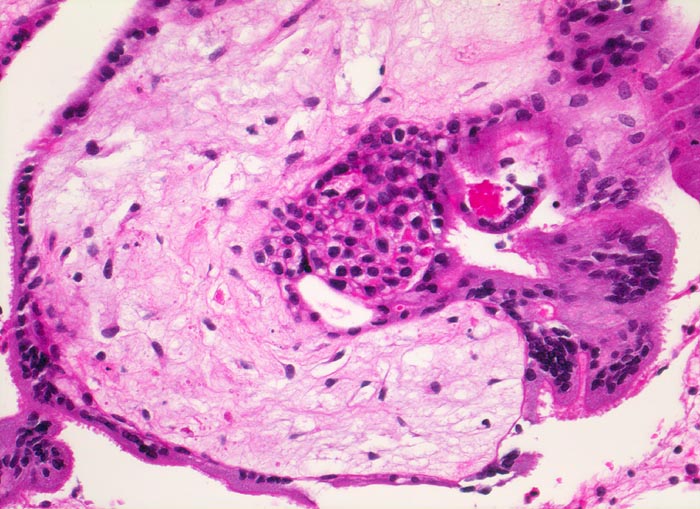

Morphologische Merkmale:

• Vergrösserte Plazentarzotten mit hydropischem Zottenstroma.

• Vereinzelt Zytotrophoblasteinschlüsse im Stroma.

• Vorwiegend einschichtiges Zytotrophoblastepithel ohne Atypien und mehrkerniger Synzytiotrophoblast. Physiologische polare Trophoblastproliferate.

Chromosomenaberrationen verursachen nicht nur beim Feten, sondern auch an der Chorionzotte morphologisch fassbare Entwicklungsstörungen: mangelnde Verzweigungen, wandernde Trophoblastzellen im Stroma, mangelhafte Vaskularisation, hydropische Alteration des Stromas und herdförmige Atrophie oder auch Hyperplasie des Trophoblasten sind typische Befunde bei einer Chromosomenaberration. Aborte mit Triploidie zeigen in der grossen Mehrzahl das Bild einer Partialmole. Eine Tetraploidie kann das Bild einer Windmole (=Windei), einer Embryonalmole oder seltener einer Partialmole verursachen. Autosomale Trisomien können ebenfalls als Windmole oder als Embryonalmole imponieren. In nur etwa 25% aller Spontanaborte sind bei der pathomorphologischen Untersuchung ein Embryo, Embryofragmente oder ein Nabelschnuranteil nachweisbar. Die morphologische Untersuchung des Abortmaterials stellt eine wichtige Ergänzung zu den klinischen Befunden dar.